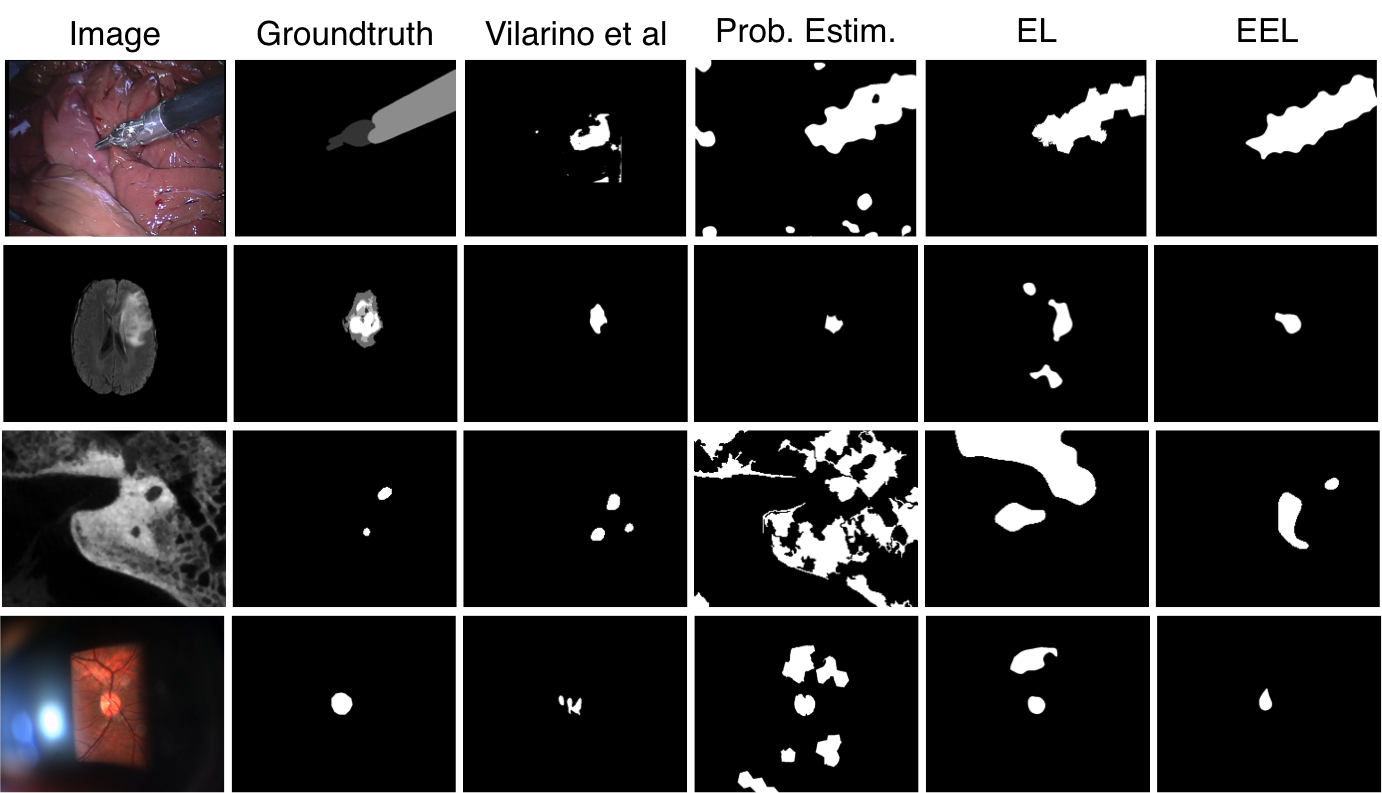

Results – Annotation accuracy: Table 1 reports the Area Under the Curve (AUC) and the F-score performances of each method applied to each dataset. In general, we report that the proposed combined label estimation and EEL function provide the highest AUC and F-score values across the tested sequences. Fig. 4 visually depicts example frames from each sequence and the outcome of each method, as well as the ground truth. To generate these binary images, a %5 false positive threshold was applied (i.e. threshold was determined using the ground truth). One can see that in cases where the object to segment occupies large areas of the image, as is the case for the surgical instrument, both the traditional loss approach and that of [15] do not perform as well since they treat significant portions of the background as positive samples during their respective learning phases.

We evaluated each of the above mentioned methods on 4 very different image sequences (see Fig. 1 for examples): (1) a 3D brain MRI containing a tumor to annotate from the BRATS challenge [10] consisting of 73 slices, (2) a 30 frame surgical video sequence from the MICCAI EndoVision challenge 111Endoscopic vision challenge: https://endovis.grand-challenge.org where a surgical instrument must be annotated, (3) a 95-slice 3D CT scan where a cochlea must be annotated and (4) a slit-lamp video recording (195 frames) of a human retina where the optic disk must be segmented. Pixel-wise annotated ground truth on all frames of each sequence was either available or produced by a domain expert. In all sequences, one and only one object is present throughout the sequence.